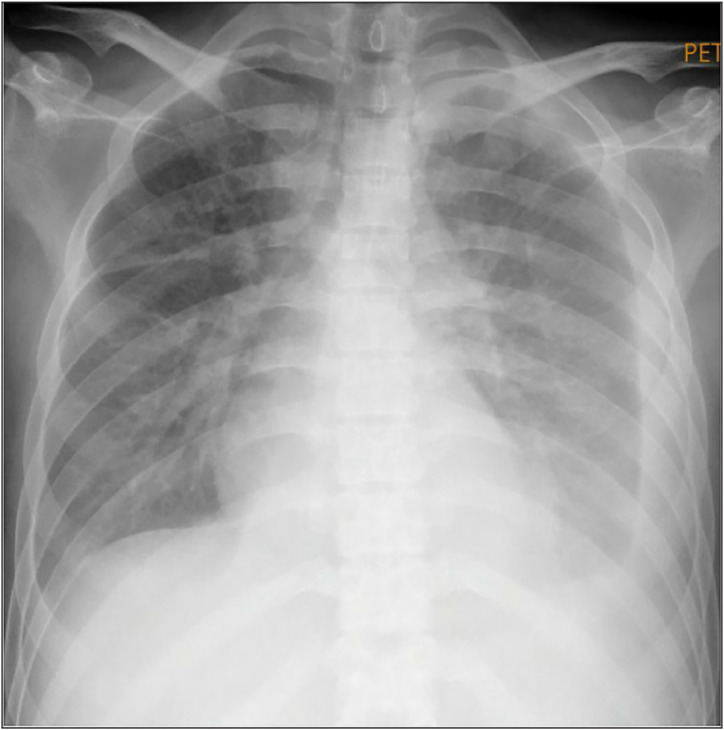

Case presentation: A 27-year-old male presented with massive head and neck swelling, initially suspected to be superior vena cava syndrome (SVCS). Other symptoms included non-scarring alopecia, prolonged fever, oral ulcers, a history of hyperpigmented skin lesions, and progressive lower extremity weakness with edema. Hematological findings revealed persistent pancytopenia (anemia, leukopenia, and thrombocytopenia). Laboratory investigations demonstrated elevated muscle injury markers, including aspartate aminotransferase predominance and elevated creatine kinase. Immunological analysis showed a negative antinuclear antibody by indirect immunofluorescence, high anti-dsDNA titers, and normal complement levels. Bone marrow biopsy revealed trilineage dysplasia with macrophage activation, suggesting underlying hematologic involvement. Contrast-enhanced head and neck computed tomography ruled out SVCS, showing only diffuse muscle and subcutaneous edema. Based on the constellation of clinical, hematological, and imaging findings, the patient was diagnosed with myositis-associated SLE. The therapeutic approach included total plasma exchange (TPE), high-dose corticosteroid pulse therapy, and immunosuppressive induction therapy. Within 1 month of hospitalization, the patient demonstrated significant clinical and laboratory improvement and was subsequently transitioned to maintenance therapy with hydroxychloroquine (200 mg once daily), methylprednisolone (8 mg daily in a tapering regimen), and mycophenolate mofetil (500 mg twice daily). The patient achieved a lupus low disease activity state at follow-up.